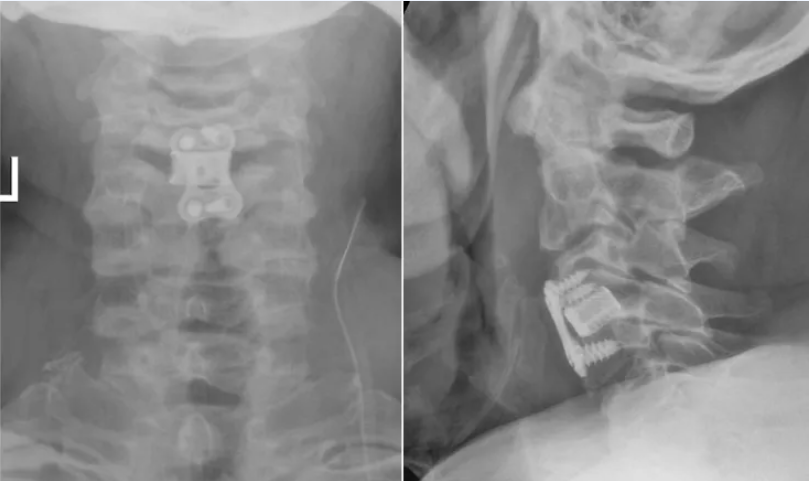

脊髓型颈椎病是危害最严重的一类颈椎病,其病变进展隐匿但后果严重,早期常表现为肢体麻木、步态异常,晚期可出现瘫痪、二便功能障碍等并发症。针对患者病情,骨科团队展开了缜密的术前讨论。考虑到传统开放手术创伤较大、恢复周期长,加之患者年龄偏大,对手术耐受性有一定要求,团队最终讨论确定采用国际公认的颈椎病手术“金标准”——颈椎前路椎间盘切除融合术(ACDF)为患者治疗。该术式通过颈部前方微小切口,精准切除病变椎间盘及骨赘,解除脊髓与神经根压迫,同时植入融合器并进行内固定,重建颈椎稳定性,具有创伤小、减压确切、恢复快等显著优势。

手术在麻醉科与手术室的密切配合下顺利开展。骨科团队凭借丰富的临床经验和娴熟的操作技巧,通过约5厘米的微小切口,精准建立手术通道,清晰显露病变节段。术中,团队仔细分离颈部血管、神经等组织,彻底清除突出的椎间盘组织及压迫脊髓的骨赘,随后精准植入椎间融合器并完成内固定。整个手术过程视野清晰、操作精准,历时仅1小时余,术中出血量不足20毫升。

术后,在骨科医护团队的精心照料和个性化康复指导下,患者恢复情况超出预期。术后第一天即可佩戴颈托下床活动,下肢麻木、沉重感明显缓解。看着自己多年的病痛得以解除,患者及家属对骨科团队表达了由衷的感谢。